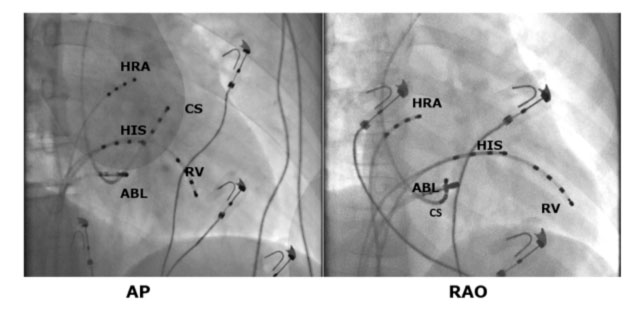

Gli elettrocateteri diagnostici quadripolari vengono posizionati a livello dell’atrio destro alto, del fascio di His, in apice del ventricolo destro e nel seno coronarico (vena cardiaca che circonda in solco atrio ventricolare sinistro e permette di registrare l’attività elettrica nella parte sinistra del cuore).

In genere, lo studio elettrofisiologico endocavitario precede l’ablazione della via accessoria permettendo la sua esatta localizzazione. La procedura di ablazione viene eseguita in anestesia locale ed una blanda sedazione farmacologica. Si ottengono mediante la tecnica di Seldinger plurimi accessi venosi (in genere femorale destro e succlavio sinistro). Qualora la via accessoria abbia una localizzazione sinistra si posiziona anche un accesso arterioso (arteria femorale destra) al fine di poter permettere l’ablazione mediante approccio transaortico. In alternativa è possibile raggiungere le camere cardiache sinistre mediante la puntura transettale.